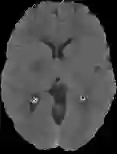

Accurate infarct segmentation in non-contrast CT (NCCT) images is a crucial step toward computer-aided acute ischemic stroke (AIS) assessment. In clinical practice, bilateral symmetric comparison of brain hemispheres is usually used to locate pathological abnormalities. Recent research has explored asymmetries to assist with AIS segmentation. However, most previous symmetry-based work mixed different types of asymmetries when evaluating their contribution to AIS. In this paper, we propose a novel Asymmetry Disentanglement Network (ADN) to automatically separate pathological asymmetries and intrinsic anatomical asymmetries in NCCTs for more effective and interpretable AIS segmentation. ADN first performs asymmetry disentanglement based on input NCCTs, which produces different types of 3D asymmetry maps. Then a synthetic, intrinsic-asymmetry-compensated and pathology-asymmetry-salient NCCT volume is generated and later used as input to a segmentation network. The training of ADN incorporates domain knowledge and adopts a tissue-type aware regularization loss function to encourage clinically-meaningful pathological asymmetry extraction. Coupled with an unsupervised 3D transformation network, ADN achieves state-of-the-art AIS segmentation performance on a public NCCT dataset. In addition to the superior performance, we believe the learned clinically-interpretable asymmetry maps can also provide insights towards a better understanding of AIS assessment. Our code is available at https://github.com/nihaomiao/MICCAI22_ADN.